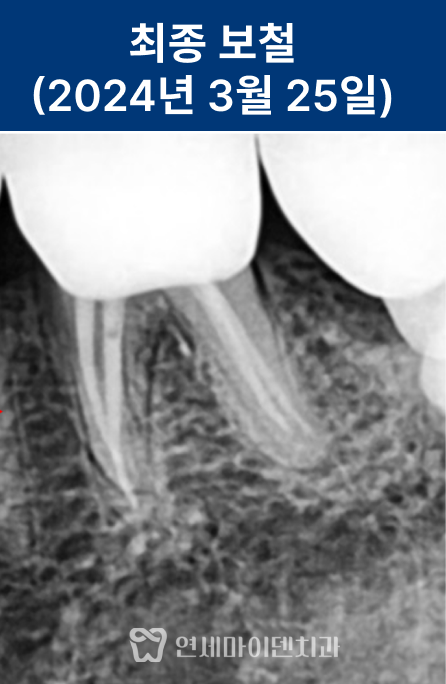

신경치료를 통해 염증 부위를 제거하고,

레진으로 내부를 밀봉한 뒤 크라운을 수복했습니다.

치근까지 염증이 진행되기 전 내원하신 덕분에

발치 없이 치아를 보존할 수 있었습니다.

최종 보철물은 귀국 시기에 맞춰 맞춤 제작하여 완성했습니다.